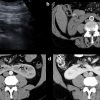

III. Chẩn đoán siêu âm

– Thận xoa trục, 2 cực dưới thận liên tục với nhau vắt ngang qua phía trước cột sống bởi nhu mô thận hay tổ chức xơ.

– Trên lát cắt dọc: không thấy rõ ranh giới cực dưới 2 thận.

– Trên lát cắt ngang qua đường giữa: 2 thận dính nhau, vắt ngang qua cột sống, phía trước động mạch chủ bụng.

– Có thể kèm theo các bất thường bất thường đường bài xuất, thận đôi, sỏi, nang thận hoặc u thận, sỏi gây giãn đường bài xuất.

=> Case lâm sàng 1: